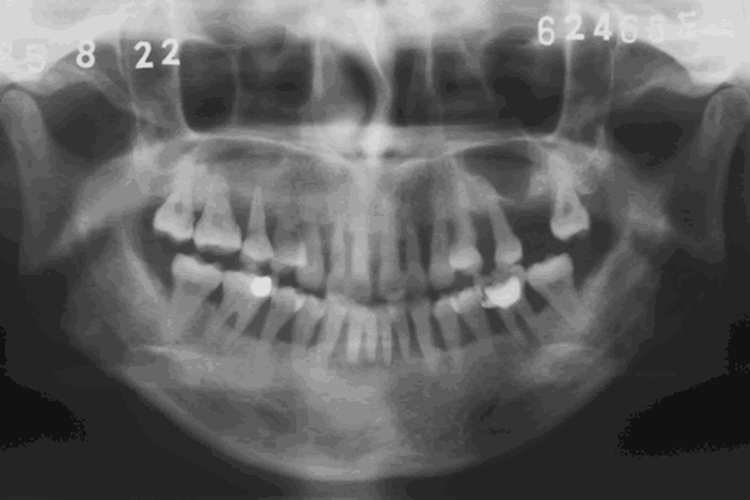

水平型吸收是常见的牙槽骨吸收方式,X线片影像学表现为牙槽间隔、唇颊侧或舌腭侧牙槽骨从嵴顶往根尖方向呈横向的高度减低,吸收程度比较均匀一致,形成骨上袋。垂直型吸收也称角形吸收,表现为局部牙槽骨或牙槽间隔的一侧,沿牙体长轴自冠方斜向根端吸收,与牙根面之间形成一定角度的骨缺损,最终造成牙槽骨吸收。